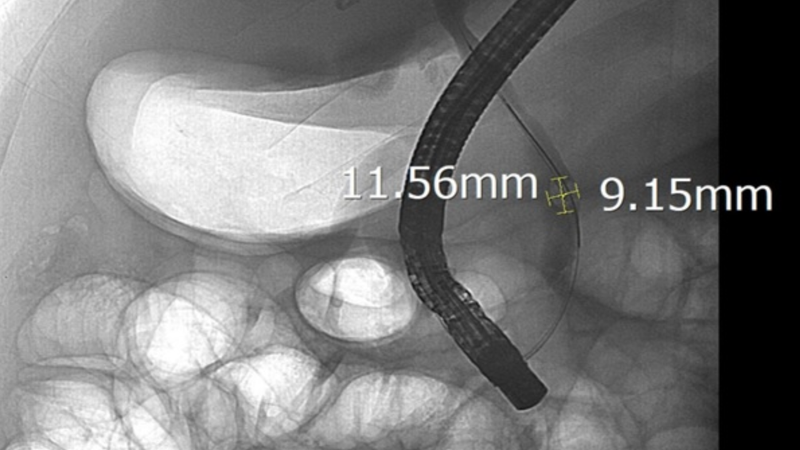

Trong quá trình can thiệp, ê kíp đã tiếp cận chính xác vị trí tắc nghẽn và lấy thành công viên sỏi kích thước lên tới 11,5 x 9 mm. Ngay sau khi sỏi được lấy ra, dòng mật được lưu thông trở lại, tình trạng tắc mật được giải phóng hoàn toàn.

Trường hợp sỏi ống mật chủ “khủng” 11,5 x 9 mm gây tắc mật nặng ở bệnh nhân 44 tuổi là lời cảnh báo không nên chủ quan với các dấu hiệu bất thường như đau bụng, vàng da kéo dài. Việc thăm khám sớm và xử trí kịp thời giúp người bệnh tránh được các biến chứng và nâng cao hiệu quả điều trị.